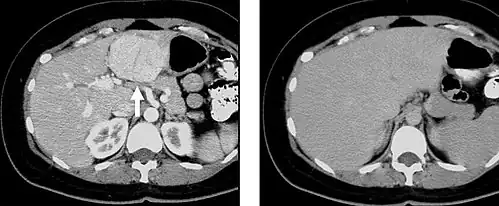

Computed tomography

When evaluating hepatic masses by abdominal computed tomography (CT), it can be advantageous to have both late arterial and portal venous phase images since some tumors enhance briskly during the arterial phase (hepatocellular carcinoma, hepatic adenoma, follicular nodular hyperplasia (FNH), and hypervascular metastasis), but maybe occult or difficult to characterize on portal venous phase imaging alone. However, it should be stressed that the addition of late arterial phase images is only indicated if one of these tumors is suspected, or if there is a need for further characterization of a hepatic mass, since the large majority of patients will not benefit from the addition of this phase. In addition, if there is a need to definitively characterize a hepatic mass, MRI is generally more sensitive and specific, with no associated radiation dose.